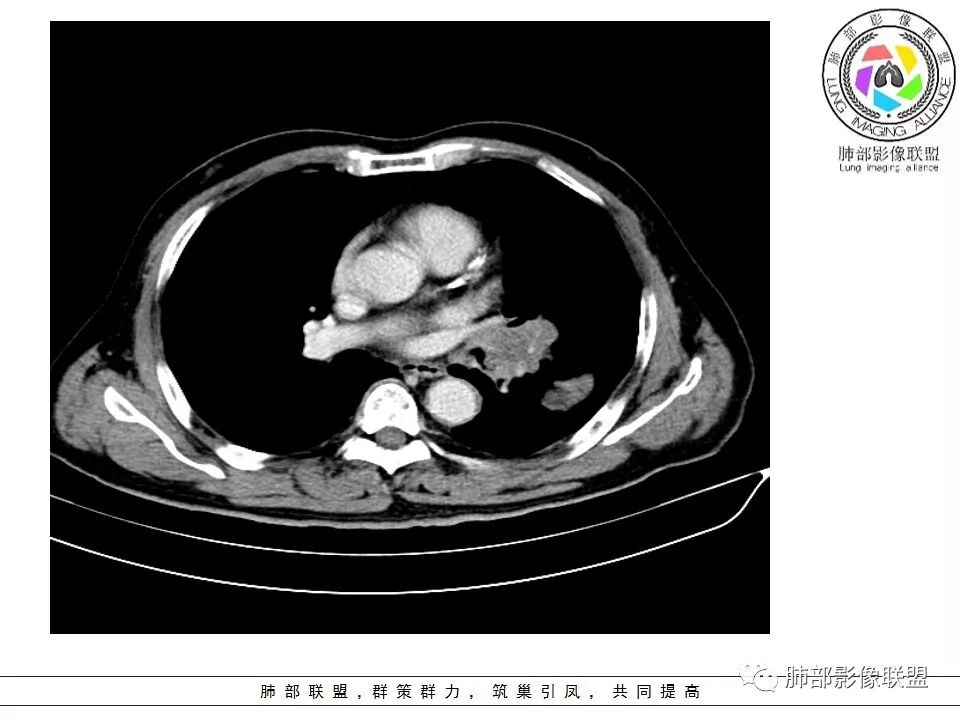

南边:与肺静脉啥关系?这样追下去是不是很恶啊

尘缘:@南边 肺静脉受侵

南边:病灶分为两大块,外围囊实性大肿块,支气管关系不密切,内带多发淋巴结,侵犯支气管、肺血管,恶性没问题,按理间叶为主,或不典型的癌,这不是一个中央型的肺癌,是外朝内进展的,奇怪的是边界这么清楚光滑,一般癌肉瘤、肉瘤类多,其次才是癌,远端也没有阻塞,大方向是这样,恶性,间叶来源?或者混合,恶性程度较高,鉴别就是结核,因为结核是妖

1.左肺下叶近肺门区肿块,肿块外围大,内带小,提示外围向中央生长,符合周围型SCLC沿支气管方向生长。

2.病灶边缘光滑,未见明显分叶、毛刺,符合神经内分泌癌、癌肉瘤及间叶来源肿瘤。

3.病灶内密度偏低,穿行血管未见明显异常,轻度不均匀强化,为乏血供病灶。病灶内可疑坏死区,未见空洞;乏血供符合SCLC,但坏死区不符合。

4.病灶区支气管以受压推移为主,管腔不规则,腔内通而不畅,提示病灶粘膜下为主,符合SCLC迁徙蔓延或间叶来源肿瘤。

5.病灶内有血管走行,血管局部受压,但是强化考虑为乏血供,提示病灶内肺动脉并不是供血血管,只是病灶侵袭性强把血管包埋而已,为血管包埋征;血流面光滑,血管包埋符合SCLC。

6.左肺门淋巴结肿大,与病灶局部融合分界不清,呈冰冻肺门;而纵隔内未见肿大淋巴结,冰冻肺门符合SCLC,但是病灶主体那么大,纵隔内没有明显肿大淋巴结,不是很符合SCLC娘小崽大的特点。

7.未见明显阻塞性炎症及阻塞性肺不张,更加提示病灶从外围向中央侵犯,符合SCLC罕见阻塞性肺不张。